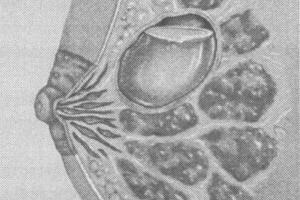

Кисты являются симптомами узловой формы мастопатии. Они образуются вследствие расширения одного из протоков молочной железы, сначала формируется капсула из соединительной ткани, ограничивающая полость, а потом в полости накапливается жидкость невоспалительного характера. По форме образования могут быть округлыми, овальными или иметь неправильную форму.

В зависимости от количества кист различают одиночное образование (солитарная киста) и множественные образования (поликистоз молочных желез). Также, в зависимости от количества полостей киста может быть однокамерной и многокамерной. Если капсула кисты изнутри имеет разрастания, в таком случае говорят об атипичной кисте.

- Многокамерная. Очень неприятный диагноз. Сначала развивается одна киста, затем зарождаются новые, рядом, после чего они сливаются. Так формируется многокамерная киста. Заболевание обнаруживается на УЗИ.

- Солитарная. Это образование, округлой формы и эластичной консистенции. Представляет собой припухлость, заполненную жидкостью различного цвета. Чем дольше киста, тем плотнее её капсула.